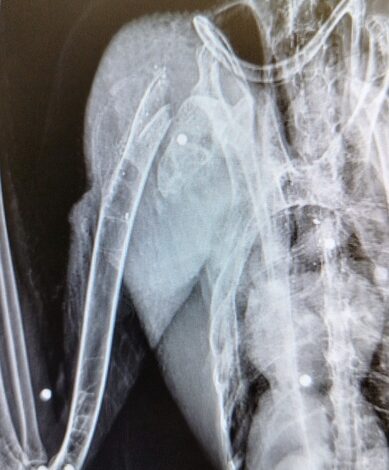

L’ibis ferito è stato trovato in un pollaio dove probabilmente cercava il suo compagno di viaggio. Due, infatti, gli esemplari avvistati in zona nei giorni scorsi. È stato un “cittadino consapevole”, ieri, a portarlo al Cras Lago di Penne, che “si è subito attivato portando il giovane esemplare in uno studio veterinario specializzato che ha subito rilevato la rottura dell’omero all’altezza della cintura scapolare e ha effettuato un delicato intervento chirurgico per tentare di restituire all’ala le migliori funzioni per permettere all’Ibis di tornare a volare”.

La radiografia ha confermato la “presenza di numerosi pallini da caccia nel corpo del rarissimo animale protetto”. Sono stati allertati i Carabinieri forestali del Nucleo Cites, che si occuperanno delle indagini sul “folle atto di bracconaggio”, cercando anche di “verificare se l’altro esemplare inseparabile Ibis, di nome ‘Coccole’, con l’anello numero 751, sia riuscito a sopravvivere”.